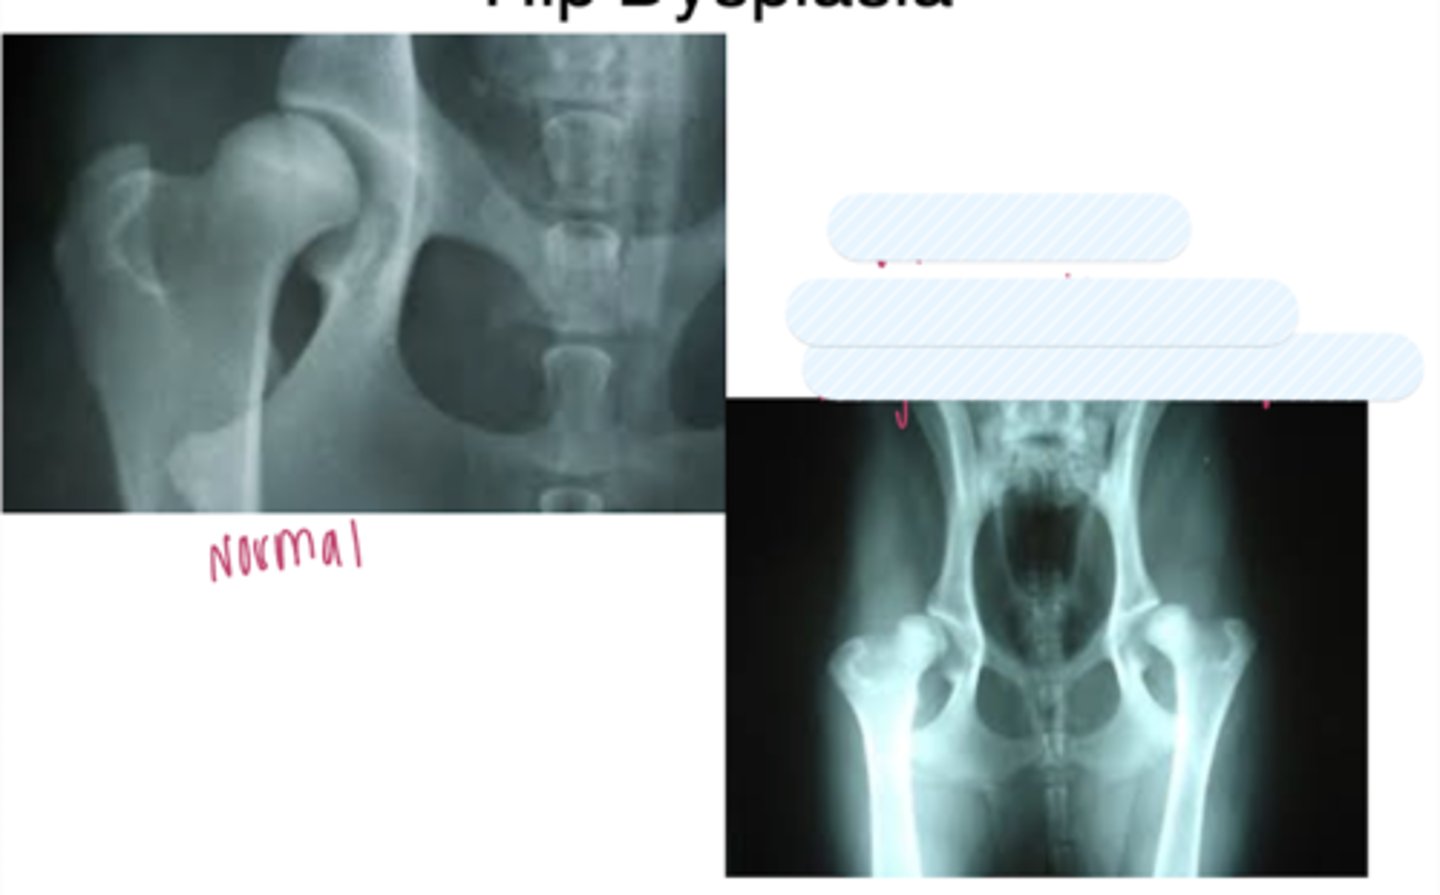

hip dysplasia on the Left photo

the L hip is worse than the R hip

very acute center edge angle

periacetabular osteotomy

used for hip dysplasia. break femur and pelvis, rotate them to provide greater joint angle